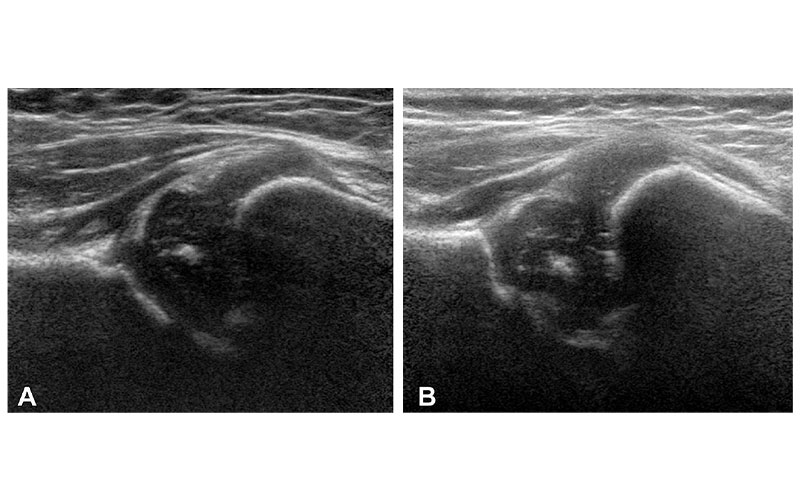

Examples of hip US images acquired with mode 2; no contrast material was used. The presented hips were (A) −1.83 (girl) and (B) +2.12 (girl) standard deviations from the mean shape.

Bonsel et al, Radiology 2022; 000:1–8 ©RSNA 2022